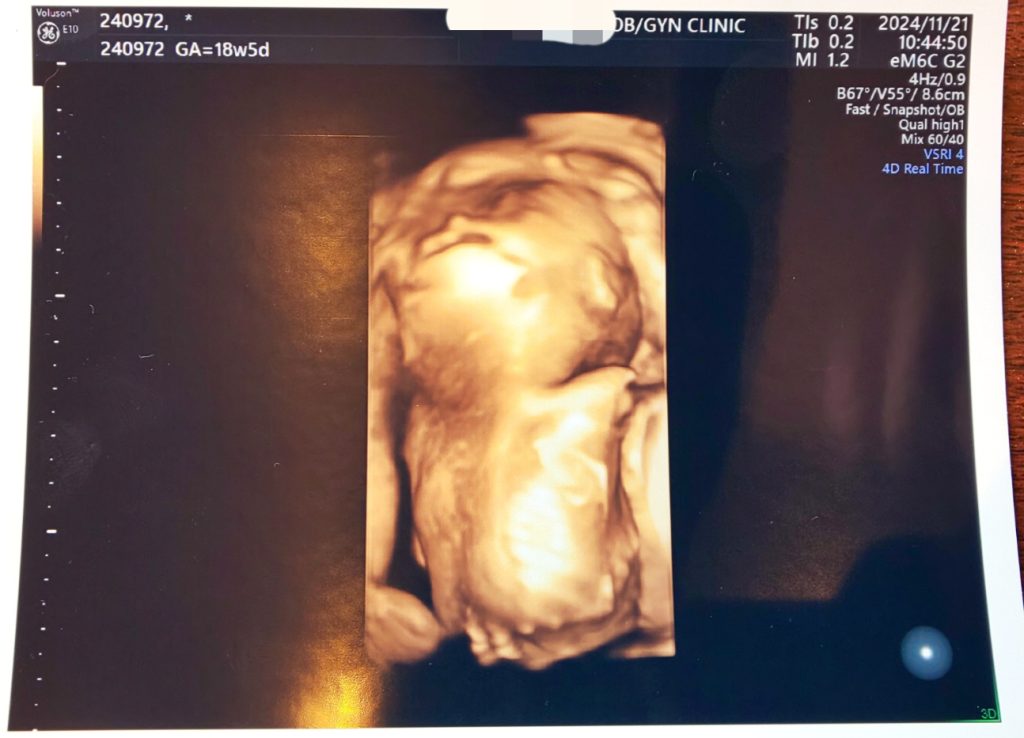

※エコー写真載せてます※

4Dのエコーでは真後ろを向いていて顔を見ることはできませんでした笑 耳や背骨も見えています。2Dエコーの時は腕を動かしたり脚をジタバタさせていました。18週に入ってからなんとなく胎動がわかるようになってきて、特に私が喋るとお腹の中がニョロニョロ動くようになりました。コールセンター勤務なので部下に指導したり、私が上席対応でお客様と直接お話することが多いのですが、その間お腹がもぞもぞ動いています笑 仰向けで寝てる時は特に胎動がわかりやすいです。